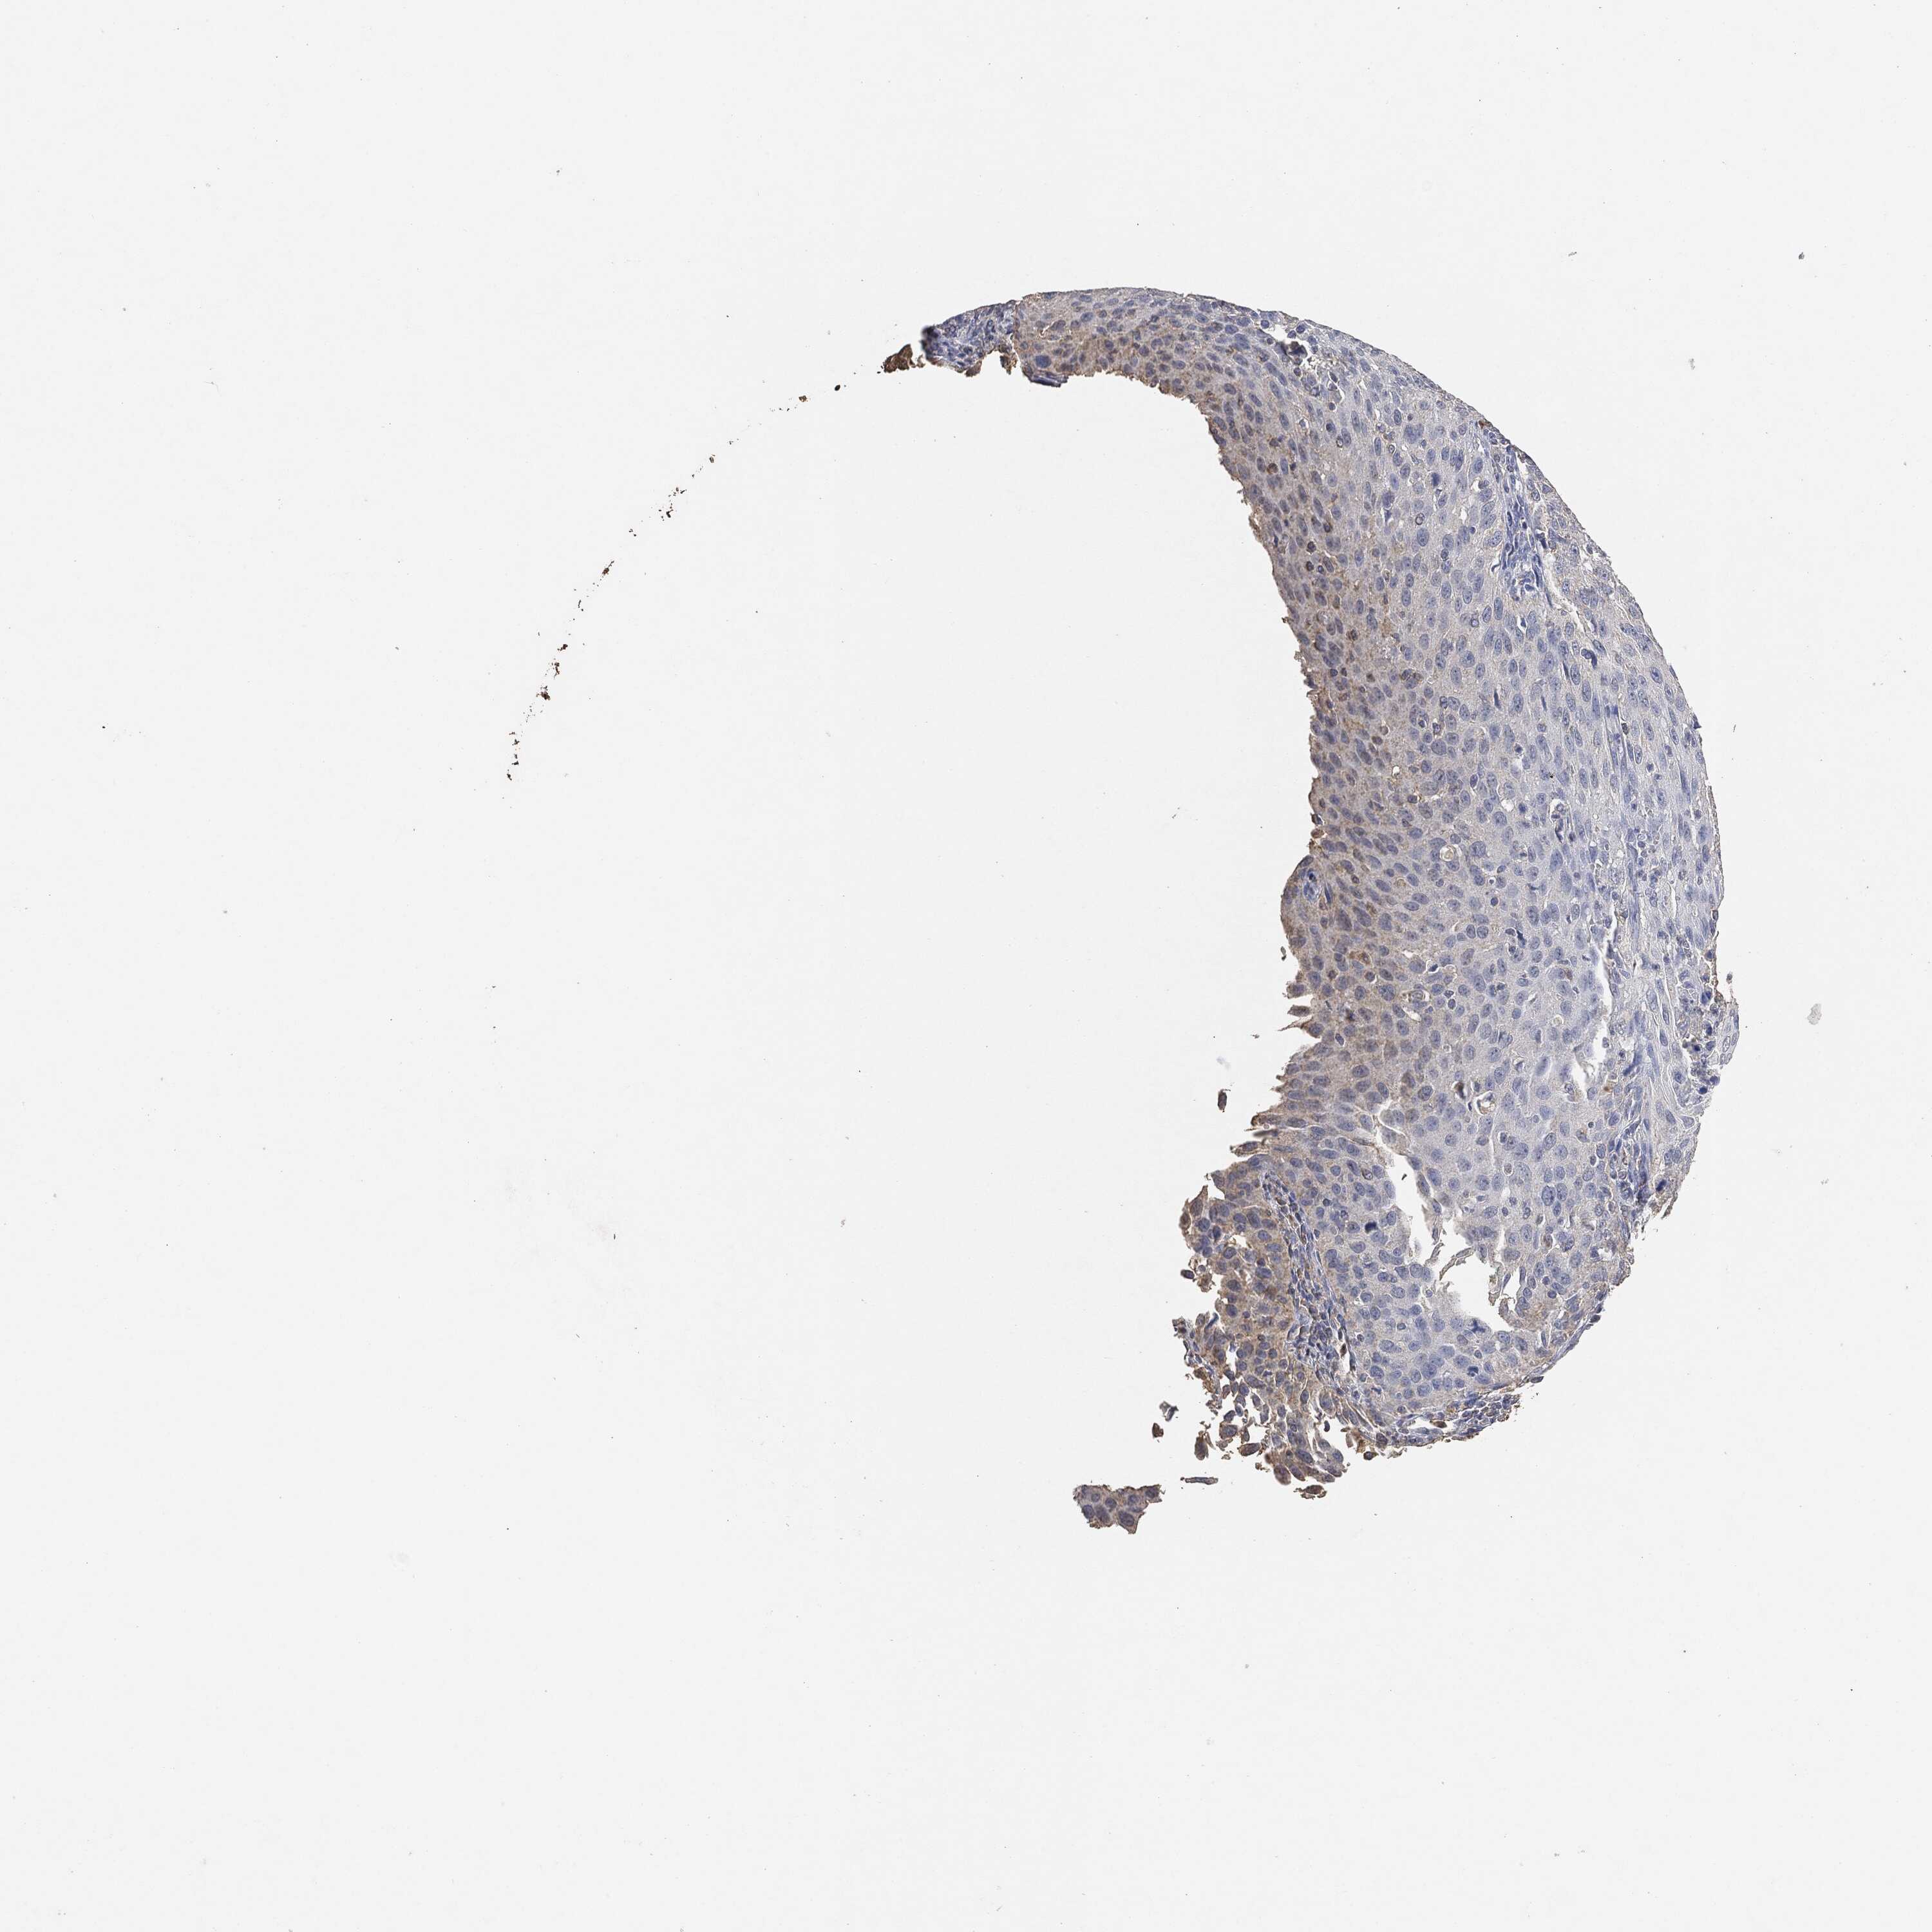

CERVICAL CANCER - Protein expressioni

A mouse-over function shows sample information and annotation data. Click on an image to view it in a full screen mode. Samples can be filtered based on level of antibody staining by selecting one or several of the following categories: high, medium, low and not detected. The assay and annotation is described here.

Note that samples used for immunohistochemistry by the Human Protein Atlas do not correspond to samples in the TCGA dataset.

Antibody stainingi

Antibody staining in the annotated cell types in the current human tissue is reported as not detected, low, medium, or high, based on conventional immunohistochemistry profiling in selected tissues. This score is based on the combination of the staining intensity and fraction of stained cells.

Each image is clickable and will lead to virtual microscopy that enables deeper exploration of all samples and also displays staining intensity scores, fraction scores and subcellular localization as well as patient and tissue information for each sample.

Staining

High

Medium

Low

Not detected

Intensity

Strong

Moderate

Weak

Negative

Quantity

>75%

75%-25%

<25%

None

Location

Nuclear

Cytoplasmic/membranous

Cytoplasmic/membranous,nuclear

Adenocarcinoma, NOS

Squamous cell carcinoma, NOS